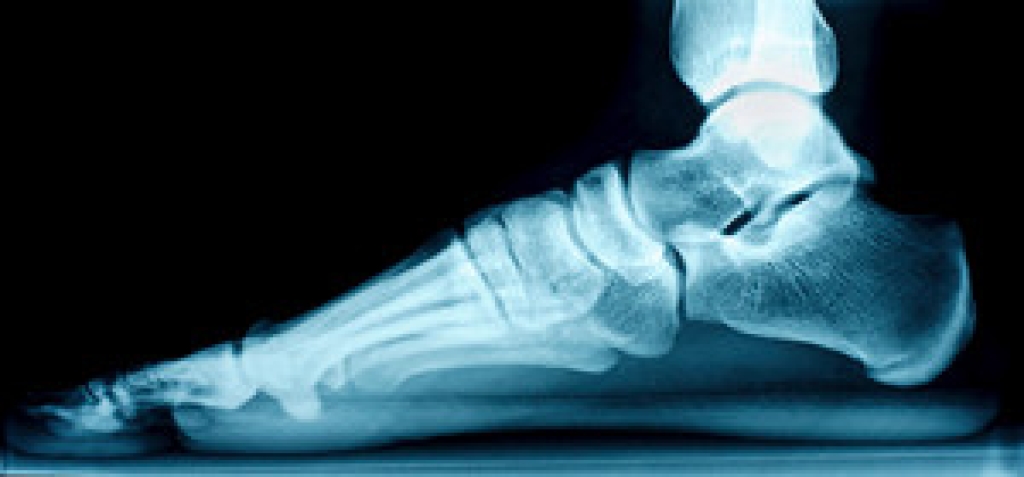

Vertical talus, often known as a rocker bottom foot, is a rare congenital condition in children where the talus bone, a key ankle component, points towards the ground instead of the toes. This misalignment leads to a stiff foot without an arch. It can occur alone or be associated with other health conditions. Diagnosis typically occurs at birth or through prenatal ultrasound. A podiatrist can assess flexibility and rigidity, using X-rays to determine the severity of misalignment. Oblique talus, a milder form of rocker bottom foot, shows misalignment only during weight-bearing. Treatment is aimed at reducing pain, advancing stability, and creating a functional foot. Non-surgical options, such as stretching or casting, may precede surgery. A series of casts can gradually improve foot flexibility. If surgery is needed, it corrects bone positions, potentially involving tendon or ligament lengthening. Post-surgery, casts, and pins are used to maintain corrections. Special shoes or braces may prevent recurrence. Understanding rocker bottom foot deformities is important for early detection and effective treatment. With a combination of non-surgical and surgical approaches, podiatrists aim to ensure pain-free, stable, and functional feet for optimal childhood development. Regular follow-up visits can help to monitor growth and address issues promptly. It is suggested that you make an appointment with a podiatrist to discuss the treatment schedule for your child.

- Vertical talus, where the talus bone forms in the wrong position causing other bones in the foot to line up improperly, the front of the foot to point up, and the bottom of the foot to stiffen, with no arch, and to curve out.